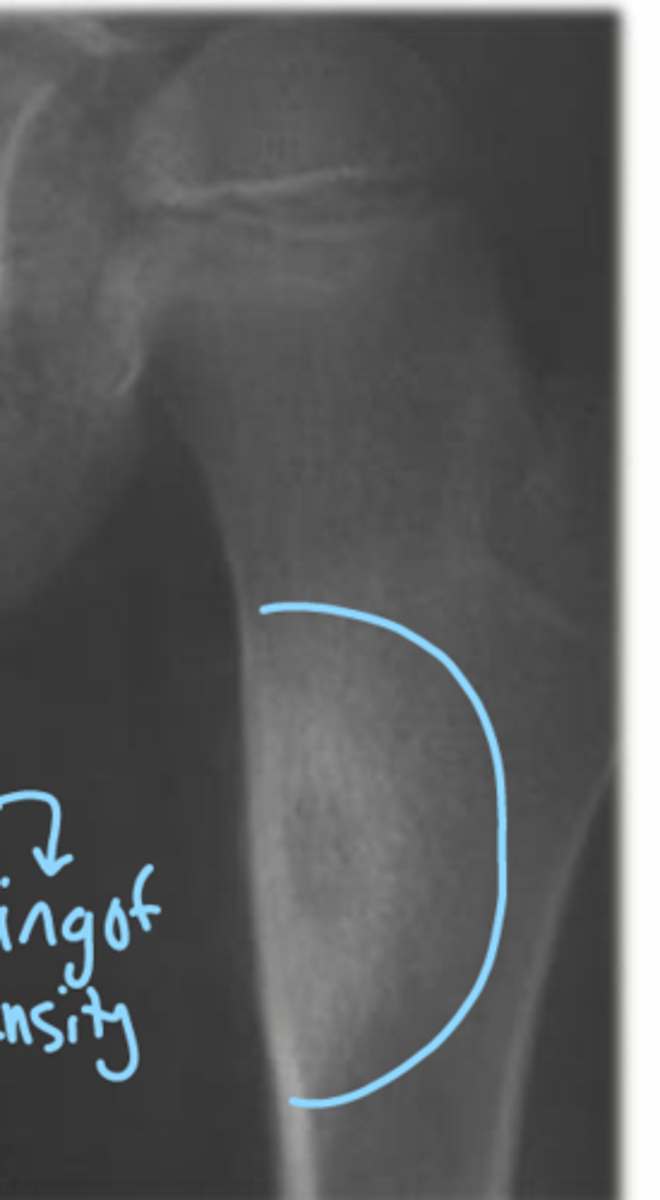

A 16 year old male patient presents to your office and the x-ray shows this (picture)? what does he have?

osteoid osteoma

someone with osteoid osteoma may complain of pain during what time of the day?

night